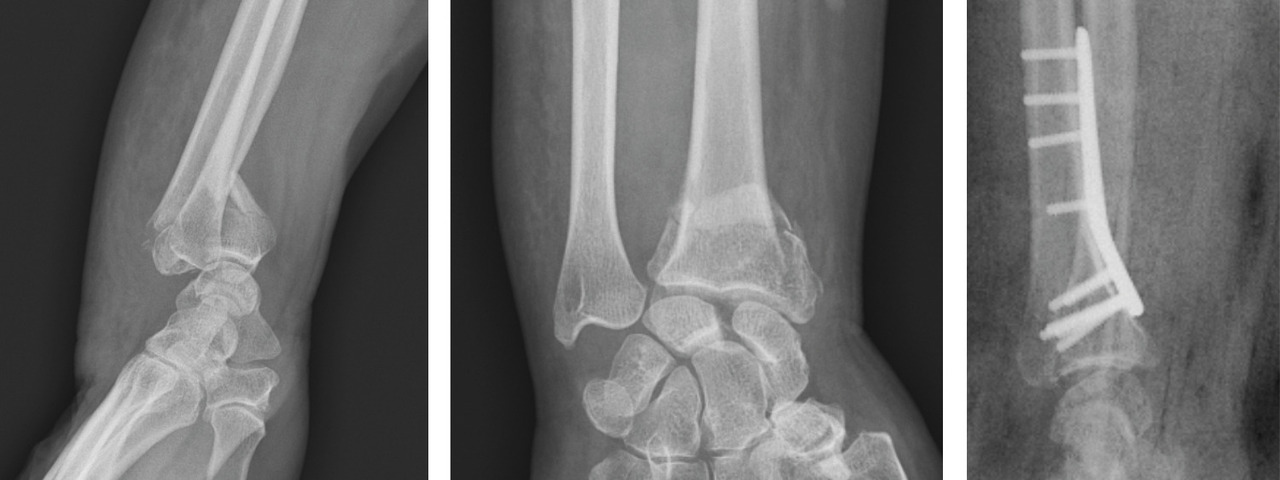

Au terme de ce bilan clinique, des radiographies standard du poignet avec 4 incidences sont incontournables : face et profil stricts et, trop souvent oubliés, de trois quarts latéral et médial. Ces dernières incidences sont en particulier utiles pour analyser l’étendue de la comminution métaphysaire dans le plan horizontal et pour dépister les refends articulaires.8

L’analyse précise et détaillée des clichés radiographiques renseigne sur les critères morphologiques importants détaillés plus haut : l’inclinaison frontale, l’inclinaison sagittale et l’index radio-ulnaire distal. Il faut également apprécier les caractéristiques métaphysaire et épiphysaire de la fracture et la présence de lésions associées : comminution, nombre et déplacement des fragments articulaires, fractures de l’extrémité inférieure de l’ulna, fractures des os du carpe, lésions ligamentaires intracarpiennes ou de l’articulation radio-ulnaire distale.

Le premier correspond aux critères morphologiques de la fracture, avec son caractère déplacé ou non, la direction du déplacement et son potentiel d’instabilité. Une fracture de l’extrémité inférieure du radius est considérée « déplacée » en cas de modification d’inclinaison de l’épiphyse radiale de plus de 5° dans le plan frontal ou sagittal et/ou un raccourcissement de 3 mm ou plus et/ou un déplacement articulaire supérieur ou égal à 2 mm. Par ailleurs, le déplacement initial important (> 20° de bascule, raccourcissement d’au moins 4 mm du radius), la comminution métaphysaire et une atteinte articulaire significative par sa comminution ou son déplacement sont les 3 principaux facteurs d’instabilité fracturaire orientant vers une fixation chirurgicale de la fracture après réduction.